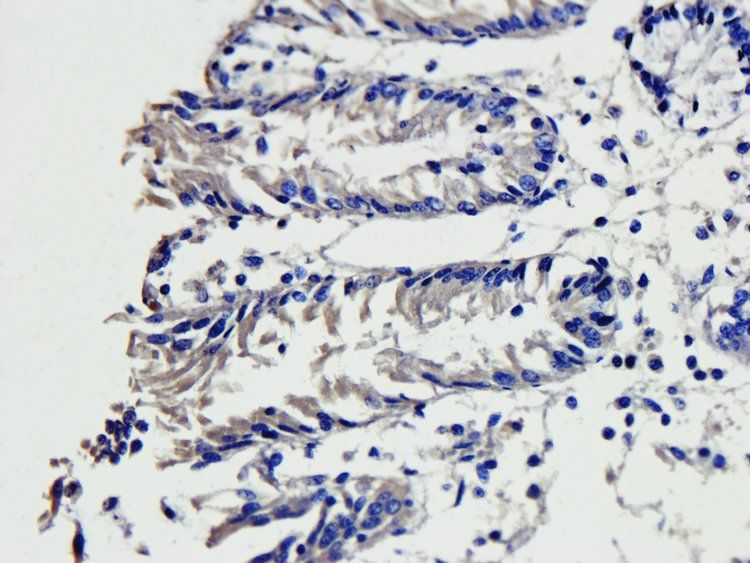

应用稀释比例:IHC-P:1:200, WB: 1:500, IF/ICC: 1:200

ELISA, ICC, IF, IHC-P, WB